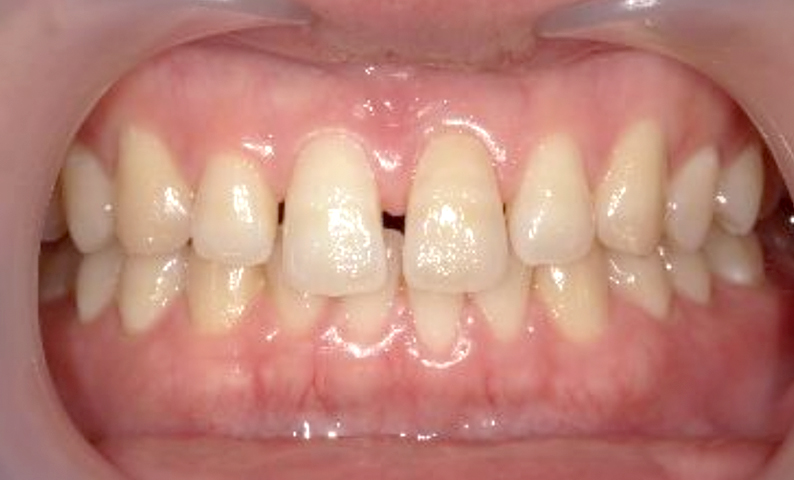

| 治療前 | 治療後 |

|---|---|

|